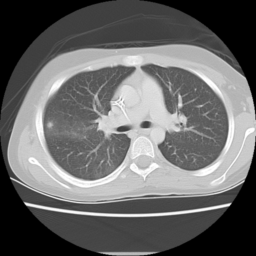

![]() |

| (a) | (b) | (c) | (d) |

Unsupervised Categorization: Our category discovery clusters are generally visually coherent within the cluster and size-balanced across clusters. However, image clusters formed only based on text information (of radiology reports) are highly unbalanced [49], with three clusters inhabiting the majority of images. Note that our method imposes no explicit constraint on the number of instances per cluster. Fig. 6 shows sample images and their top-10 associated key words from two randomly selected clusters (more results are provided in the supplementary material). The LDPO clusters are found to be clinically or semantically related to the corresponding key words, which describe presented anatomies, pathologies (e.g., adenopathy, mass), their associated attributes (e.g., bulky, frontal) and imaging protocols or properties.

The category discovery clusters employing our LDPO method are found to be more visually coherent and cluster-wise balanced in comparison to the results in [49] where clusters are formed only from text information ( radiology reports). Fig. 7 Left shows the image numbers for each cluster from the AlexNet-FC7-Topic setting. The numbers are uniformly distributed with a mean of 778 and standard deviation of 52. Fig. 7 Right illustrates the relation of clustering results derived from image cues or text reports [49]. Note that there is no instance-balance-per-cluster constraints in the LDPO clustering. The clusters in [49] are highly uneven: 3 clusters inhabit the majority of images. Fig. 6 shows sample images and top-10 associated key words from 5 randomly selected clusters (more results in the supplementary material). The LDPO clusters are found to be semantically or clinically related to the corresponding key words, containing the information of (likely appeared) anatomies, pathologies (e.g., adenopathy, mass), their attributes (e.g., bulky, frontal) and imaging protocols or properties.